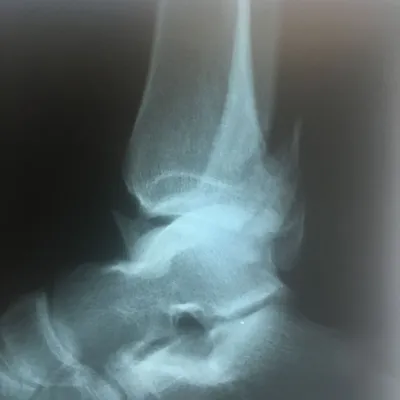

CT scan and Xray sagittal views of severly displaced posterior tibial malleolar fracture with comminution. This type of injury can cause significant problems in the future with disability if not treated with surgery to reduce the fracture and fixate.

Trimalleolar fractures involve fracture of the medial and lateral malleoli

along with a fracture of the posterior lip of the tibial

plafond; (posterior malleolar fracture). Fracture results from avulsion

by the posterior tibiofibular ligament at its site of attachment to the

tibia. The irregularity in the tibial articular surface of the tibia is

brought against the weightbearing surface of the talus and with

motion and weightbearing severe DJD develops.